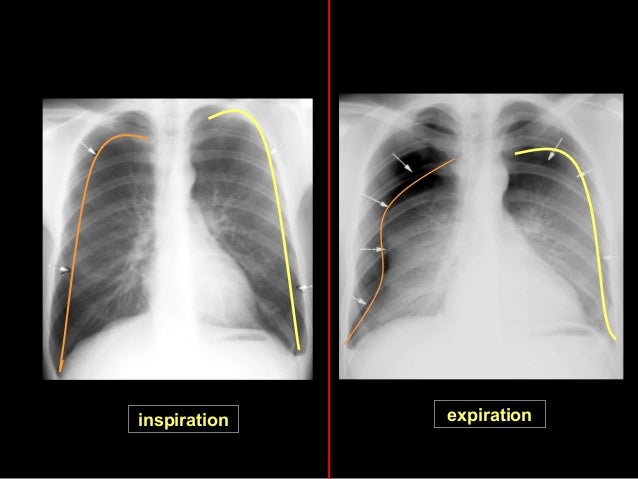

Symétrie du cliché vérifier que la radio est bien centrée en regardant si l'extrémité interne des clavicules est à équidistance des apophyses épineuses des premières vertèbres. Définition Le hile du poumon est l'emplacement des poumons dans lequel les vaisseaux pulmonaires, les nerfs, les vaisseaux lymphatiques et les bronches se rejoignent Les hiles du poumon se situent au niveau du médiastin, qui contient, entre autres, le cœurOn trouve dans les hiles du poumon la veine pulmonaire inférieure, la veine pulmonaire supérieure, le ligament triangulaire, les. Dr Hiles dynamically teaches on the finished work of the cross, the message of God's neverending love, and His grace which causes us to have an abundant life wwwlynnhilescom 1 A Study of Ezra & Nehemiah Part 26 show 563 Air Date 12 28 1230.

Médiastin et hiles pulmonaires •Lignes et bords du médiastin Bord droit T veineux brachiocéphalique D Veine cave supérieure Oreillette D Veine cave inférieure Bord gauche A sousclavière G Arc aortique = «bouton ao » Tronc pulmonaire Ventricule gauche Ligne paraoesophagienne Ligne paraaortique Crosse veine azygos. 6 pièges de la radio thorax Opacité rétrocardiaque Hiles pulmonaires symétrique (N G > D) Ascension d’une coupole diaphragmatique (N D > G) Effacement de la coupole diaphragmatique gauche Comblement de la fenêtre aorticopulmonaire Recherche systématique de fracture/lyse osseuse costale et claviculaire. Noah Hiles Verified Reporter daily allbaseball show on DK Sports Radio, which will come to you every weekday morning I will talk with my good friend and fellow Pirates beat writer Alex Stumpf The Pirates are half way through the season Alex and I give our midseason awards for both the Pirates and the all of baseball.

IV VALEUR SEMIOLOGIQUE (5)2Syndrome de condensation pulmonaire rétractile• Compression extrinsèque / adénopathies, tumeurs thymiques, goitre• Compression intrinsèques / corps étrangers intra bronchiques, cancers bronchopulmonaires• Toutes causes d’encombrement endobronchique• Séquelles de tuberculose 75 V. Elle n’est pas bien centrée elle n’est pas réalisée en inspiration on visualise les électrodes Le cœur est gros. Les trois examens peuvent mettre en évidence des anomalies pulmonaires chez un patient atteint d'asbestose La radiographie et la scanographie permettent seulement d'observer des opacités anormales au niveau de la plèvre, mais cellesci pourraient être causées par la présence d'autres corps étrangers.